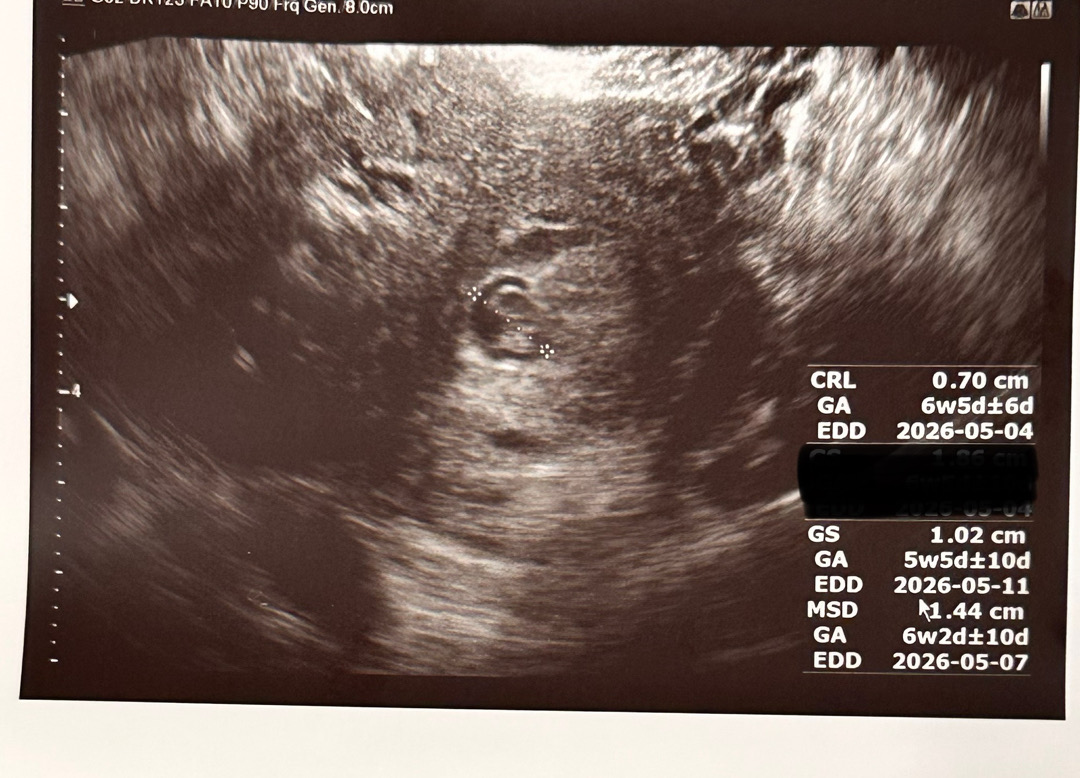

막생으로는 이제 8주되네요. 관계일은 8월초 이고 착상혈은 15일에 봤어요. 병원에서는 아기크기로 6주4일정도로 다시 정정해주셨어요. 그런데 문제는 병원 두군데나 갔는데 아기에 비해 아기집이 넘 작데요.. 심장소리는 125.. 아기는 잘 크고 있는데 아기집이 더이상 안크면 결국 심장도 멈출꺼라고 합니다. 혹시 이런 경험 있으신가요?